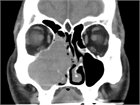

1. 鼻閉感は鼻閉塞に起因することが多いが、上咽頭疾患など鼻腔外の要因でも来し、さらに心身症や萎縮性鼻炎など、閉塞性の病変がなくても生じ得る。

1. 原疾患の病態(感染やアレルギーなど)に応じた治療を行う。鼻粘膜腫脹に対する対症療法としては、鼻処置などによる血管拡張と粘膜下浮腫の除去を行う。